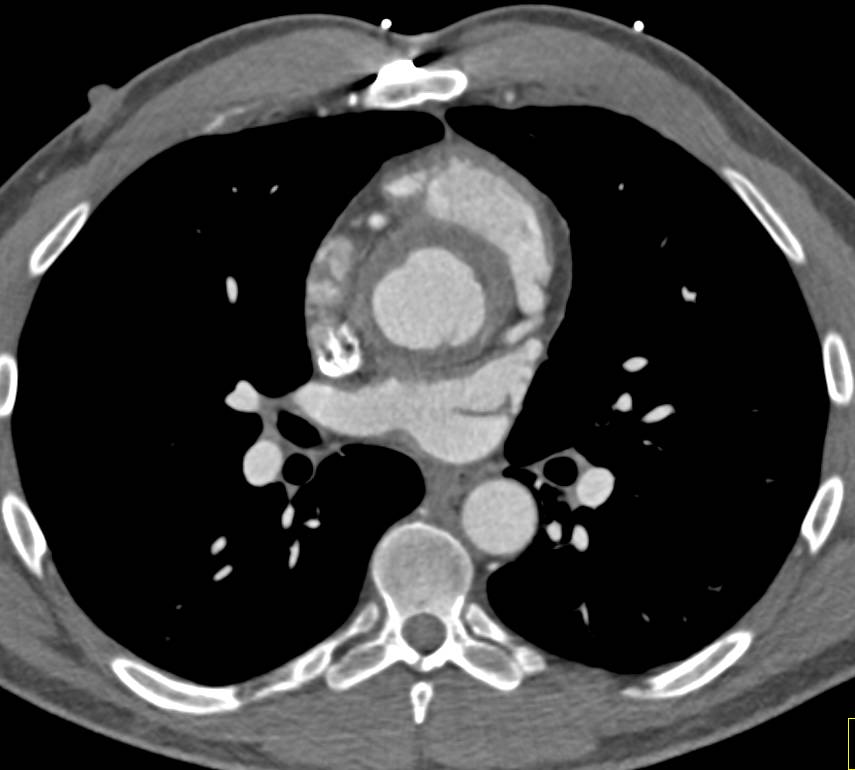

Pancreatic Cancer with Liver and Lung Metastases